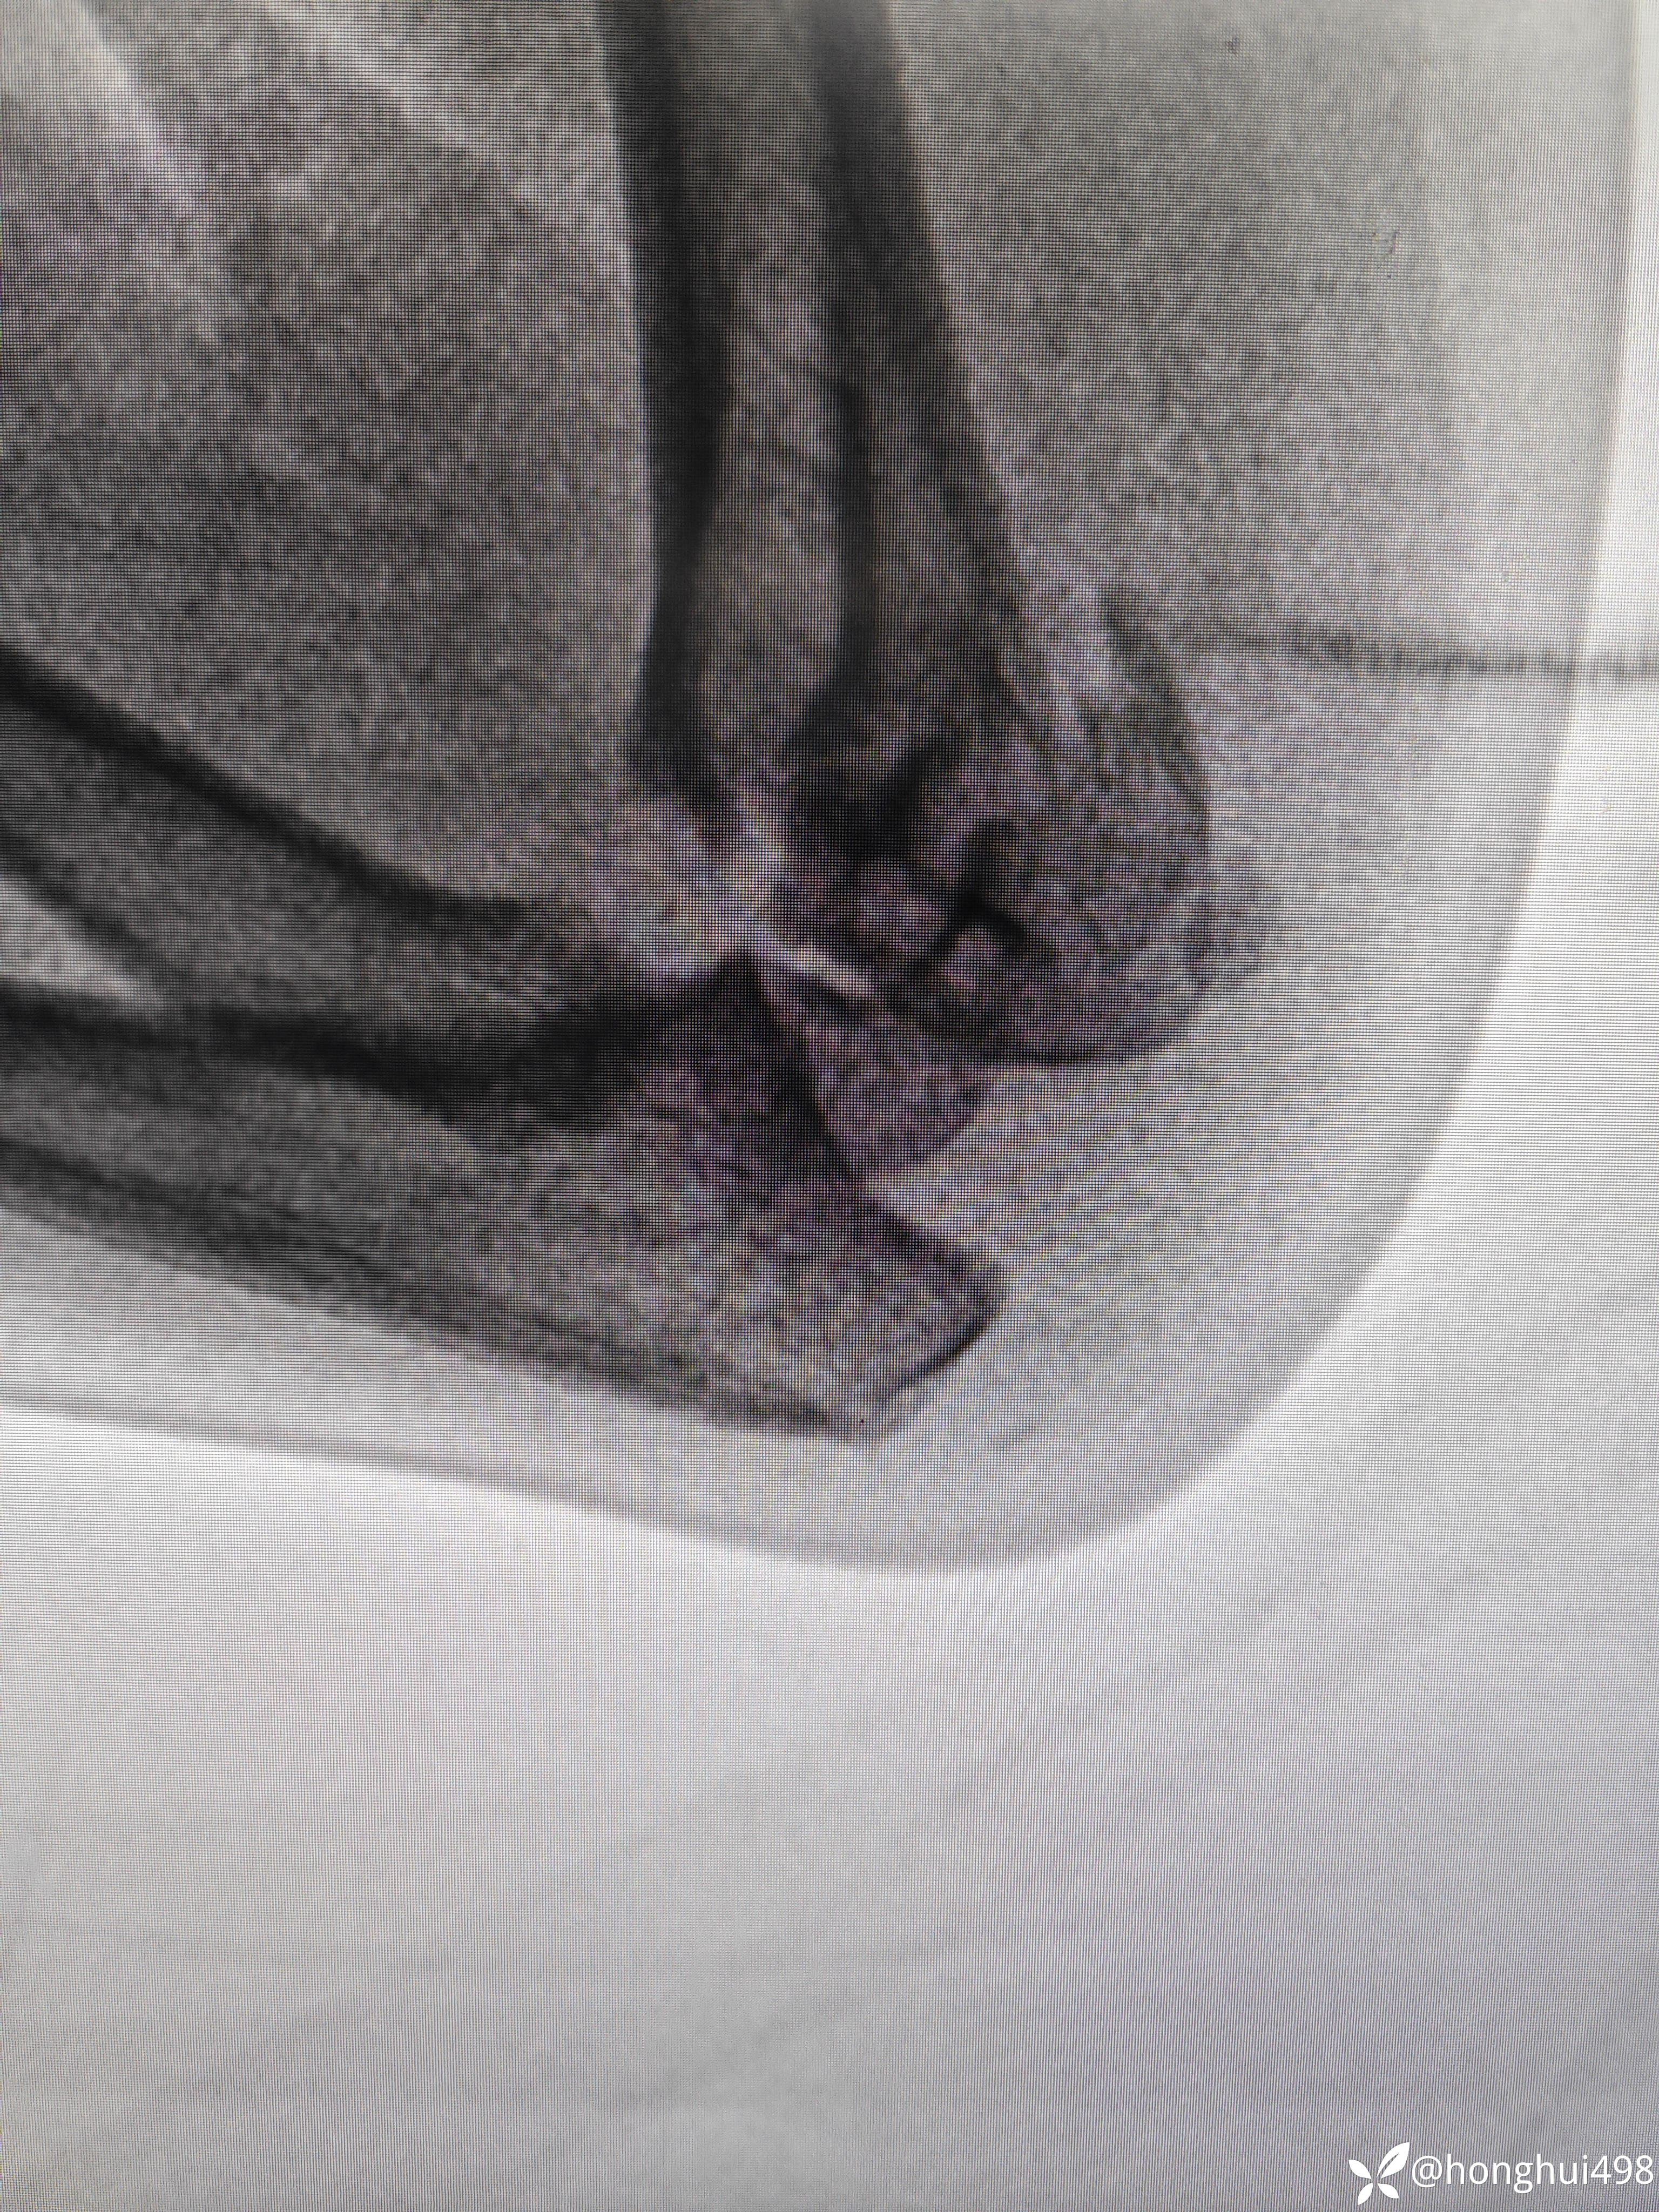

患儿女性,6岁,昨晚8点在家玩耍摔倒受伤,右肱骨髁上骨折。伤后在当地予手法复位草药外敷,伤后15小时来我院就诊,住院麻醉下闭合复位克氏针内固定。